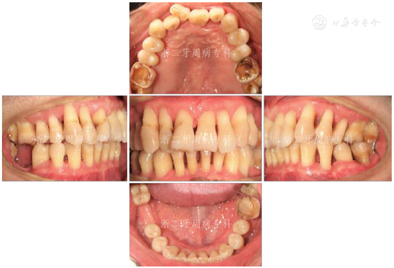

2008年9月:基础治疗完成后6个月牙周复诊,进行再评估,患者口腔卫生状况良好,牙龈炎症明显改善,PD≥7 mm的位点数从108个减少到4个,4~6 mm的位点数从61个减少到39个,平均探诊深度从7.0 mm降至3.0 mm,尤其是17远中2个位点,PD从12 mm分别降至3 mm(颊侧)与4 mm(舌侧);BOP(+)%从100%降到28.6%(图8)。各牙松动度较治疗前也明显改善,下前牙31、41仍有0.5 mm间隙。

针对深牙周袋、16、26、36、46釉质发育不全、牙列不齐、上前牙11扭转及46缺失,建议恢复16、26、36、46咬合面正常形态、牙周手术治疗、正畸及修复46,但患者暂时不考虑牙周手术、正畸和修复治疗。因此,仅进行牙周维护及11~13、21~23松动牙超级粘结剂牙周固定。

2009年4月:牙周基础治疗后1年复诊。患者口腔卫生可,牙龈色粉质韧,仅下前牙舌侧可见少量软垢,局部龈缘充血(图9),并惊喜地发现:下前牙31、41间隙已完全关闭。牙齿松动度、PD、BOP(+)%与半年前无明显变化(图10)。全口曲面体层X片示:牙槽嵴顶硬骨板较2007年12月清晰,14、17、24、34、36局部有牙槽骨修复、36根尖周骨密度增加,其余位点牙槽骨均未见进一步吸收;46缺牙区牙槽骨密度和高度增加(图11),提示牙周基础治疗后牙周状况得到了明显改善。因37、46缺失牙未及时修复,16略伸长,38近中倾斜,再次建议患者正畸治疗,直立38、压入16,排齐整平牙列,修复缺失牙37、46。患者拒绝正畸和修复治疗。予以16调磨、牙周维护治疗、35~44超级粘结剂牙周固定。